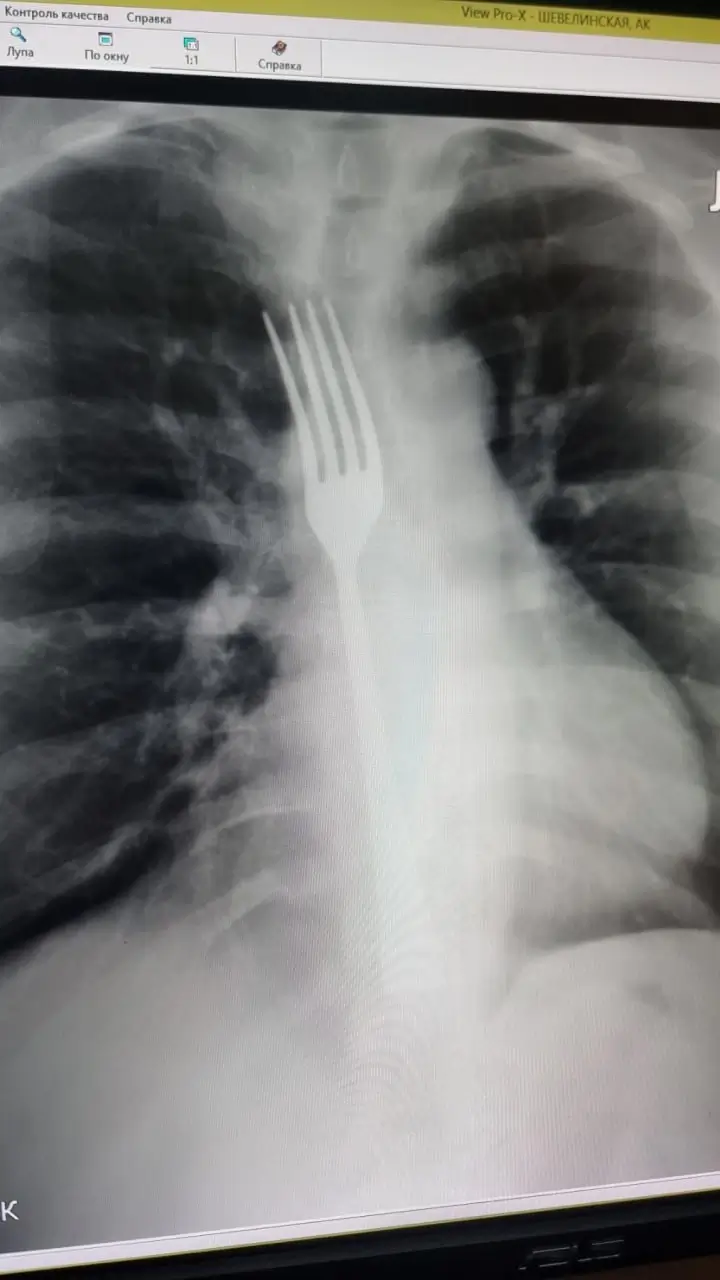

Причиной происшествия стала бытовая ситуация. Женщина почувствовала дискомфорт, который в народе называют «встал желудок», и решила прибегнуть к опасному методу самопомощи — искусственному вызову рвоты. В качестве инструмента она использовала черенок от вилки. Неосторожное движение привело к тому, что столовый прибор выскользнул и застрял глубоко в пищеводе.

Прибывшие на вызов медики экстренно доставили пострадавшую в стационар. После обследования было принято решение о немедленном хирургическом вмешательстве.

Операционная бригада в составе врачей Максима Кунцевича, Александра Кухарева и Николая Витальева провела сложную процедуру. Как пояснили специалисты, «во время ФГДС под наркозом вилку частично низвели в желудок, затем выполнили лапаротомию и гастростомию с извлечением инородного предмета».

По словам медиков, пациентке повезло, что вилка не вклинилась в стенки пищевода, так как это потребовало бы гораздо более травматичной и опасной операции. В настоящее время жизнь женщины вне опасности, она переведена в отделение для дальнейшего восстановления.